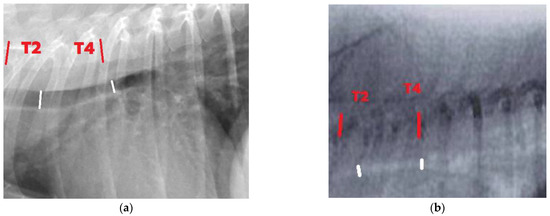

2.2. Imaging Study